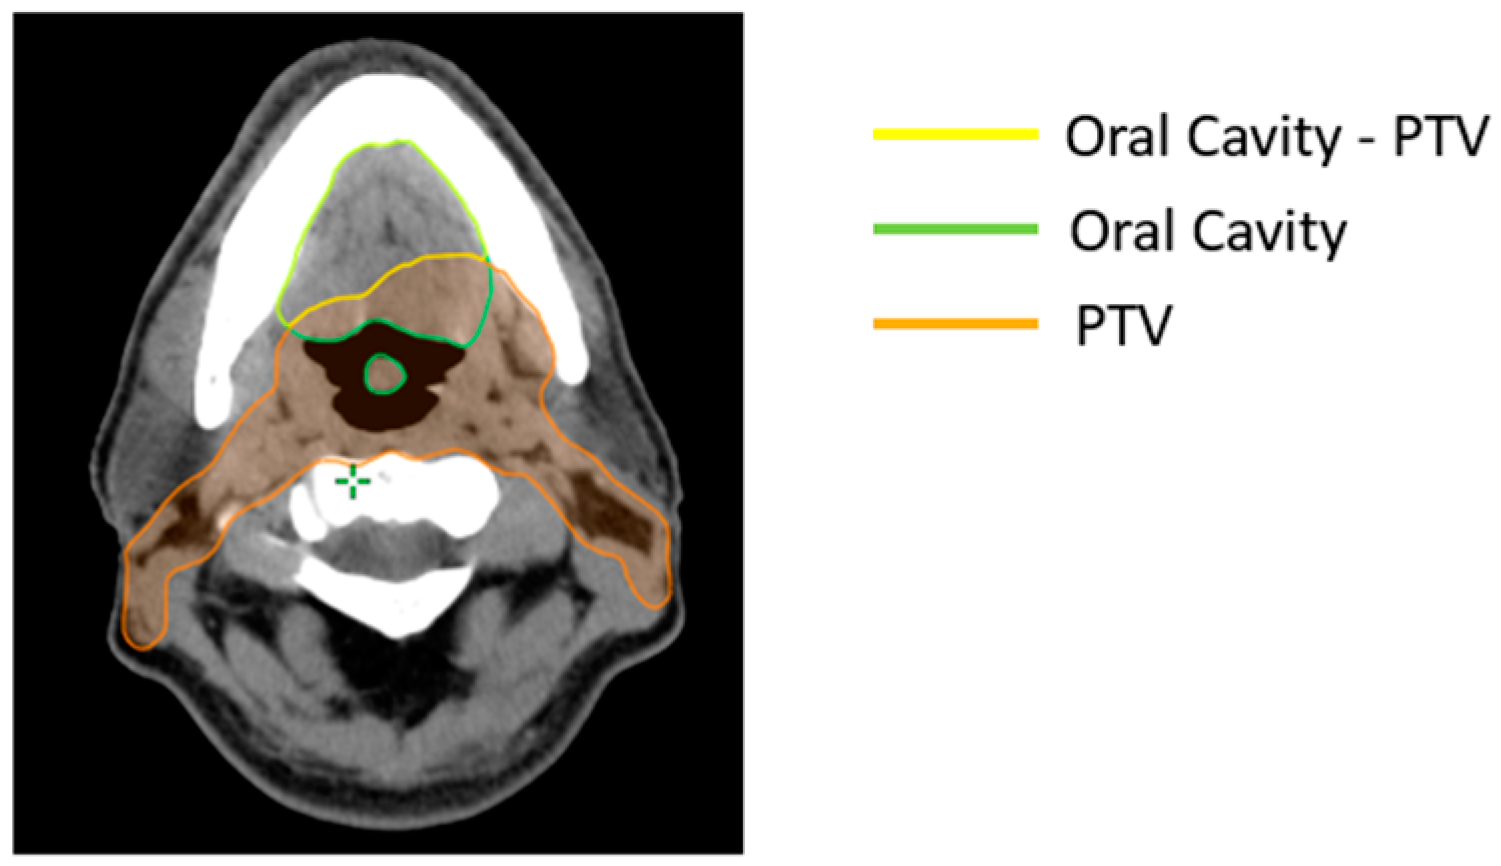

According to manufacturer suggestions, the matched OARs should not overlap with the PTV. As a result, 453 Boolean structures were created to exclude the overlap region, for all patients included in the training set (Figure 1). Therefore, the non-involved region of OARs was considered during optimization with the RapidPlan™ models.

Figure 1. Boolean structure: oral cavity minus region overlapping with the planning target volume (PTV).